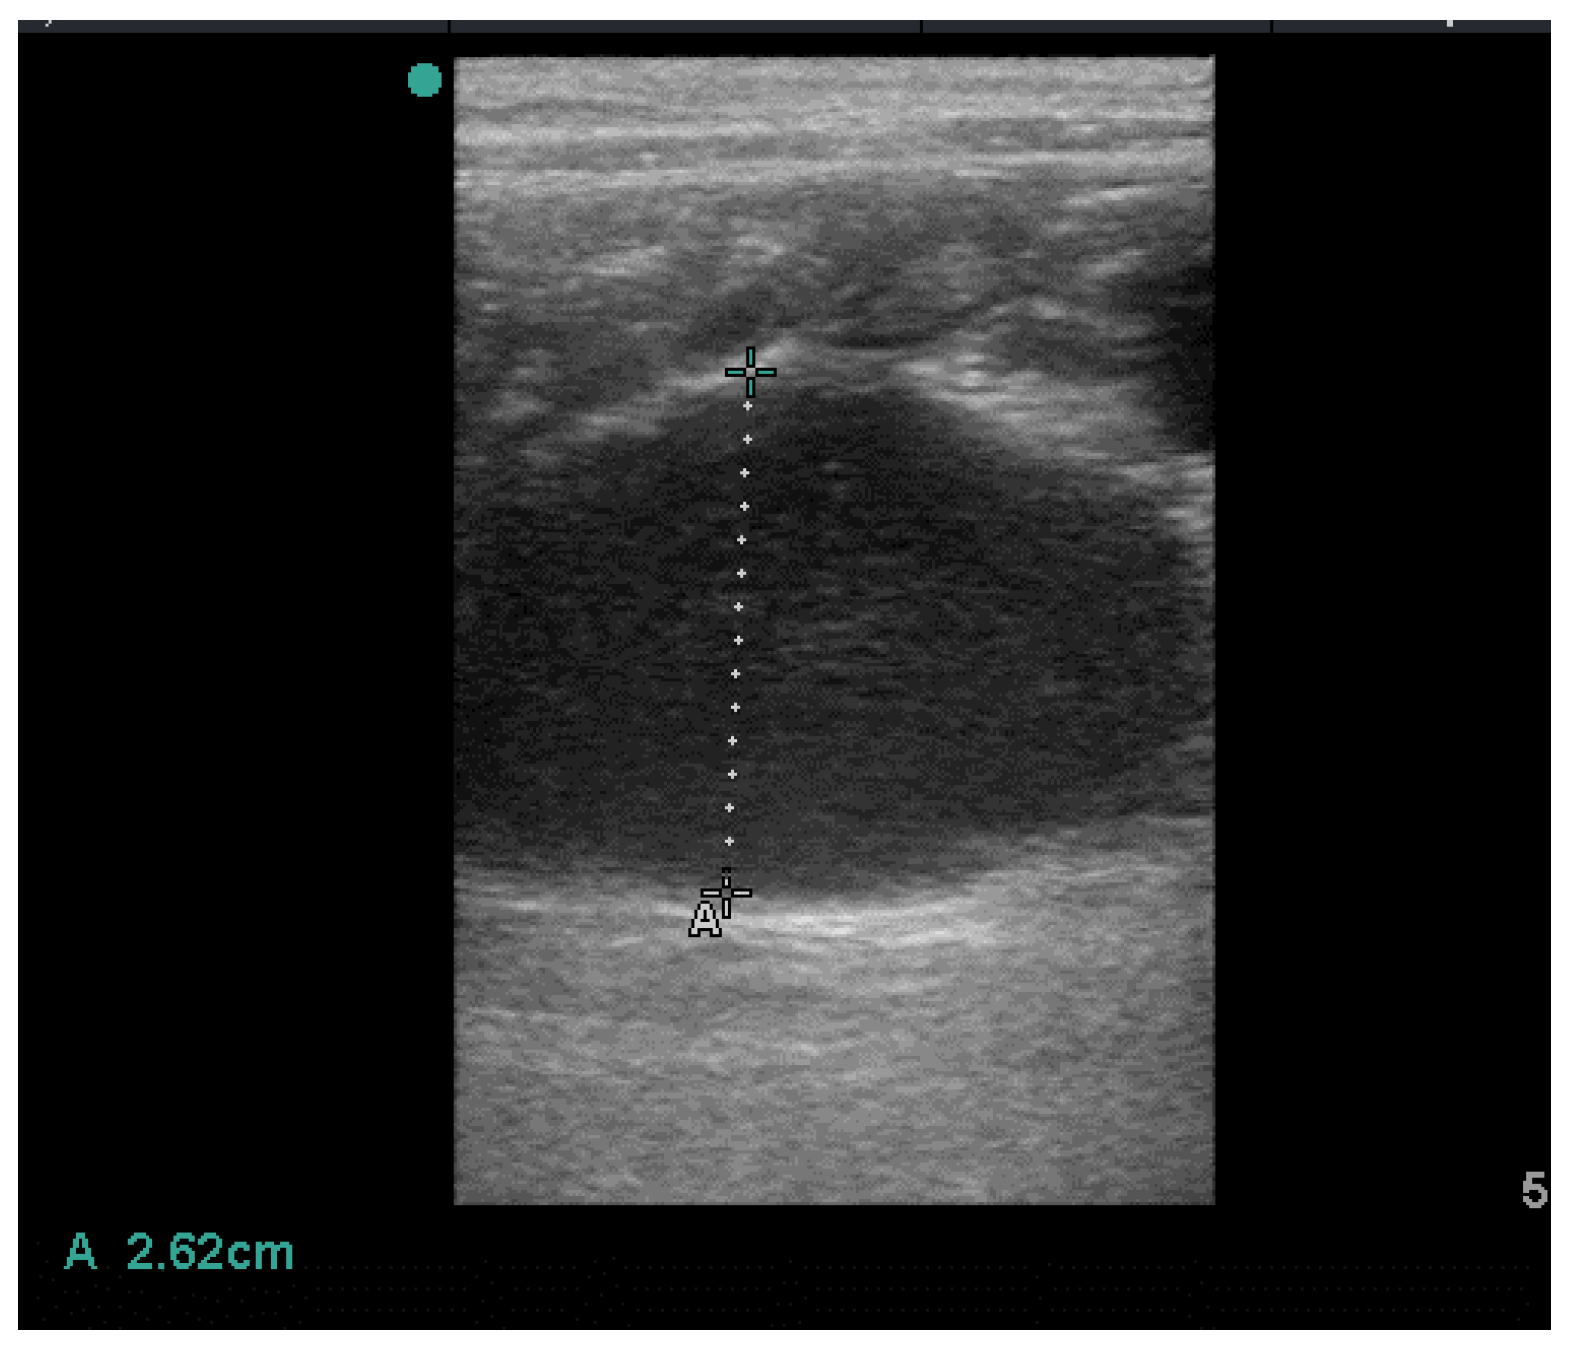

2. History and Clinical Findings

3. Treatment and Follow up